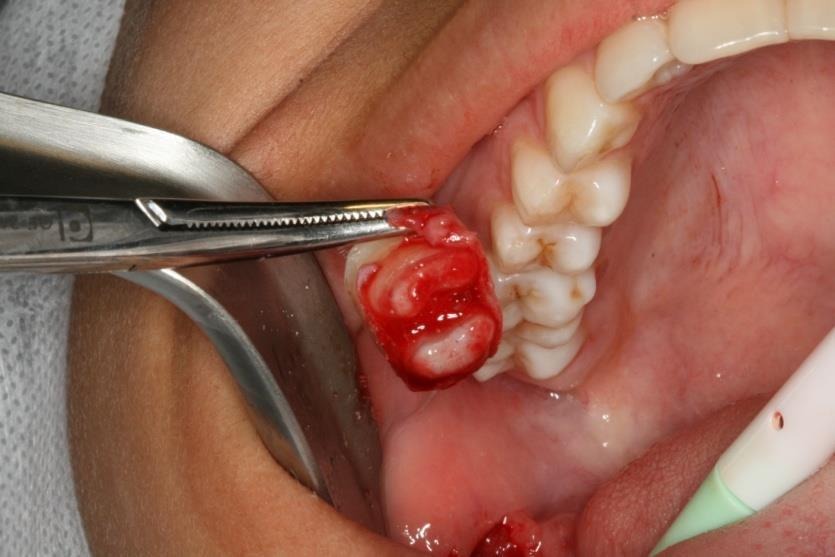

Após quinze dias foi feito a avaliação do alvéolo que receberá o dente transplantado, que neste caso não apresentou contraindicação para o procedimento. Feito a exodontia do 48 (3° molar) com o cuidado de não manipular as fibras do ligamento periodontal que são de suma importância para o sucesso do procedimento. (figura 4 e 5).

Figura 4 – Exodontia do elemento 48.

Figura 5 – retirada do elemento do alvéolo, mantendo o cuidado de não agredir as fibras do ligamento periodontal.